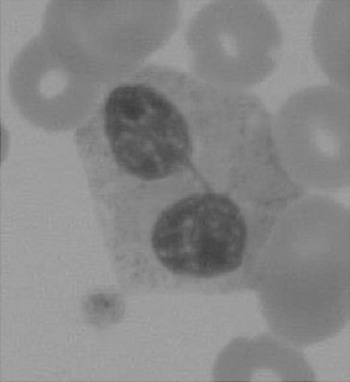

The haematologist will see multiple changes on the blood films. One such example is shown in Figure 7.4.